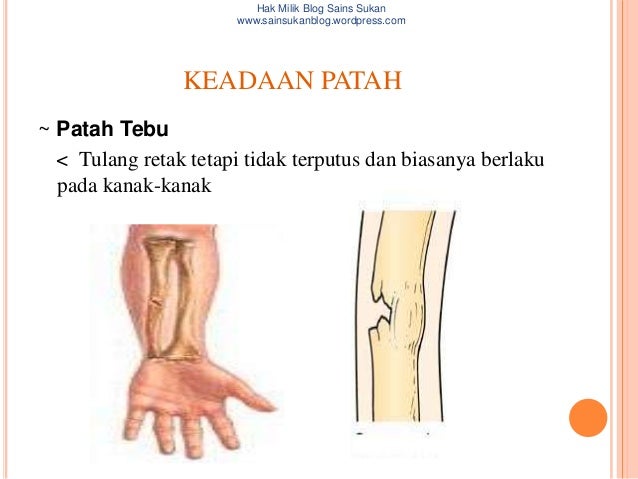

Topik 4 sains sukan

Topik 4 sains sukan